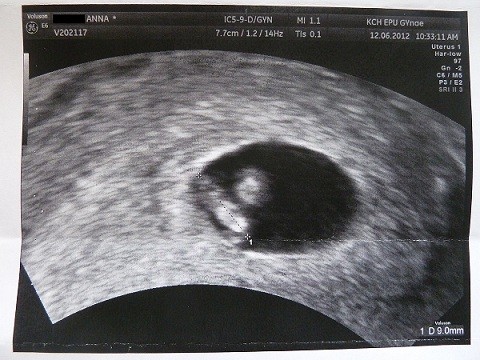

P.S: Słuchajcie zastanawia mnie ten puls, na mojej wizycie w 6t.4.d dzieciaczki miały 120/min i 121/min u was te wyniki są dużo wyższe. Czy to może oznaczać,że coś jest nie tak,czy po prostu USG było tak wcześnie,że serduszka dopiero się rozkręcały?